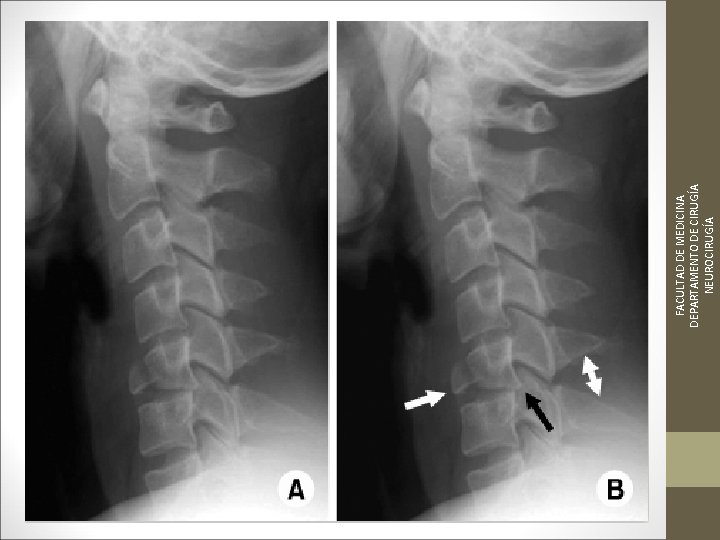

¿Qué pruebas solicitarías? Inmovilización collarín rígido Toma de constantes vitales Exploración radiológica básica: - Radiografía AP - Transoral - Lateral FACULTAD DE MEDICINA DEPARTAMENTO DE CIRUGÍA NEUROCIRUGÍA ¿Qué actitud tomarías?

Radiografía Cervical